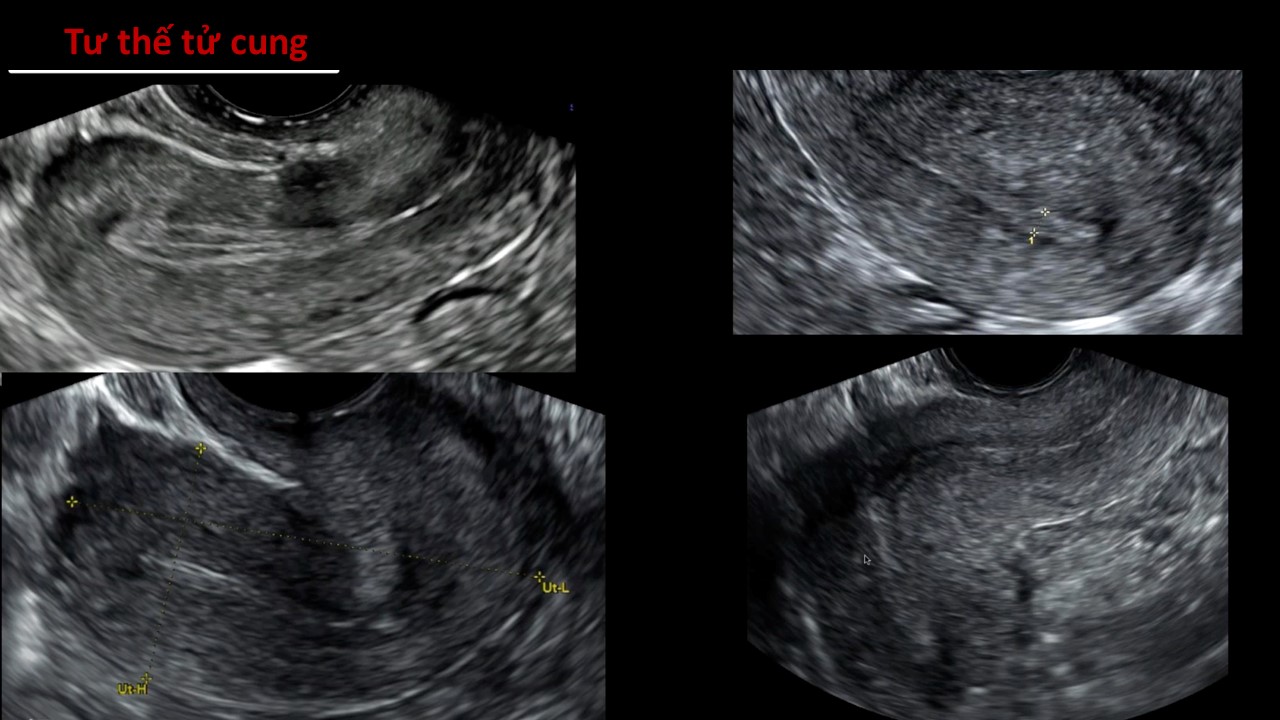

Vai trò của siêu âm trong chẩn đoán và điều trị hiếm muộn

Từ khóa: Vai trò của siêu âm trong chẩn đoán và điều trị hiếm muộn